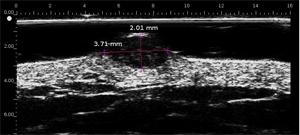

Melanomas Ecografía

Hipoecoica , con ecos de baja densidad. El eco de entrada no está muy marcado o ausente (ausencia de queratosis, ulceración) Melanoma ulcerado en el antebrazo (grosor medido a 3,68 mm en ecografía, grosor histológico). Lesión que infiltra la dermis. Melanoma en la oreja Carcinoma de células basalesCarcinoma de células basales en la frente (por encima de la arteria temporal)Carcinoma de células basales en la cara por encima del mastoidesCarcinomasuperficialCarcinoma pigmentado Nevo dérmico Lesión hipoecoica con muchos ecos, borde con la dermis adyacente mal definidoHistiocitofibroma  Lesión hipoecoica , pobremente limitada con muchos ecos.

• Melanoma superficial extenso, melanoma maligno; Índice de Breslow

• Determina el índice de Breslow para el melanoma maligno